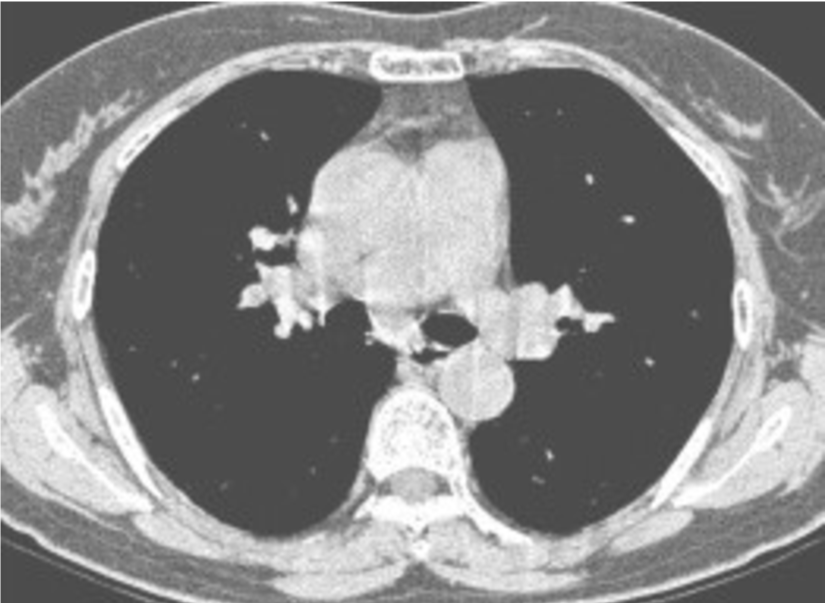

CT dataset has 349 Covid images and 397 non-Covid images [37]. Health professionals prefer breast CT scans as they carry more information compared to chest X-rays to use for medical diagnosis. Fig. 3 shows both a Covid and a non-Covid case from the CT database.

Figure 3: Two sample images from CT dataset.